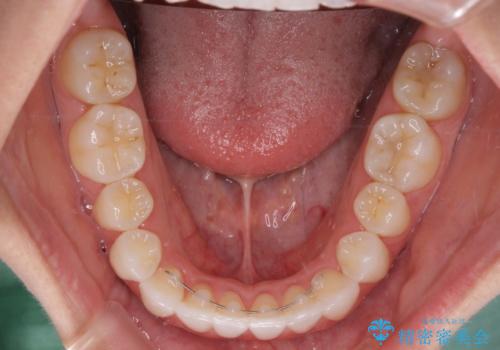

- 前歯のデコボコとクロスバイトを治したいとのことで来院された患者様です。

上下顎ともに歯列全体の側方拡大とIPR(歯と歯の間を削る)によってデコボコとクロスバイトが解消するように設計し、インビザラインにより治療を行うこととしました。

下顎骨の左側への骨格的なずれが強く、上下の正中の位置合わせや奥歯の咬み合わせ構築に苦労しました。